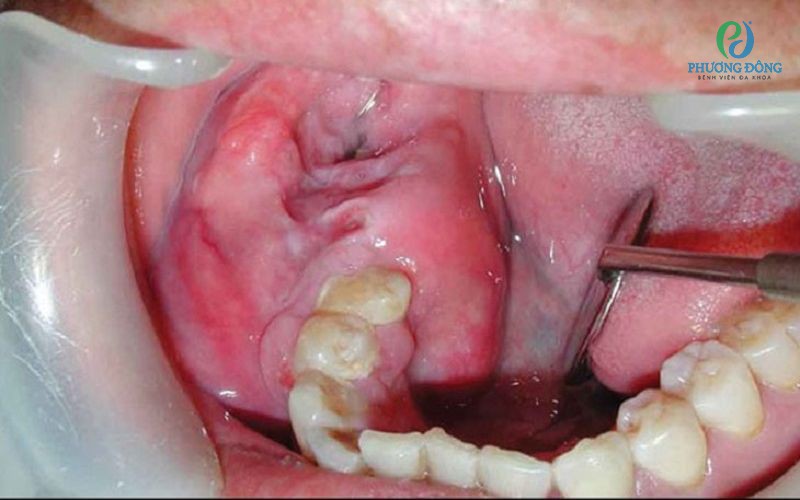

U men xương hàm là một khối u lành tính thường xuất hiện ở hàm dưới. Bệnh phát triển âm thầm khiến người bệnh khó nhận biết. Ở giai đoạn nặng, bệnh có thể khiến khuôn mặt biến dạng, thậm chí trở thành khối u ác tính và di căn sang bộ phận khác. Để hiểu rõ hơn về bệnh lý này, cùng Bệnh viện Đa khoa Phương Đông tìm hiểu chi tiết qua bài viết sau.

U men xương hàm là khối u nằm ở khoảng trống sau răng hoặc hàm, thông thường đây là khối u lành tính và phát triển khá chậm.

Bệnh gặp nhiều ở những người trẻ từ 20-30 tuổi, đặc biệt ở nam giới. U men chiếm khoảng 50% trong tổng số các khối u lành tính ở vùng xương hàm mặt. Bệnh khởi phát do các tế bào tạo nên lớp men lót bảo vệ răng nhưng vì lý do nào đó khiến chúng biệt hóa dị thường, tạo thành u men.

• Giai đoạn u hàm phá vỡ bề mặt xương: Có thể sờ thấy khối u nhưng không đau, bờ xương xung quanh mỏng và bén nhọn.

• Giai đoạn u xương hàm tạo đường rò và gây biến chứng: Lỗ rò có thể làm thủng ở mặt trong hoặc mặt ngoài miệng, từ đó để lại di chứng khó hồi phục.